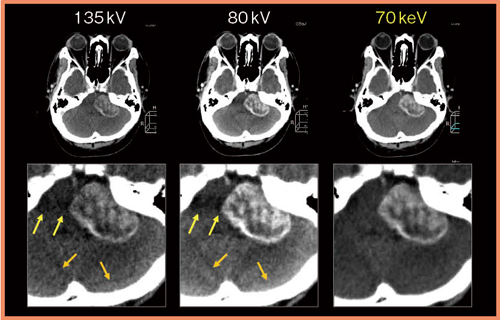

図5では,左小脳橋角部に腫瘍が認められるが,頭蓋底における帯状のビームハードニングアーチファクトと重なっている。仮想単色X線画像(図5右:70keV)を作成することで,画質を低下させることなく,アーチファクトを改善することができた。

図5 ビームハードニング効果の比較